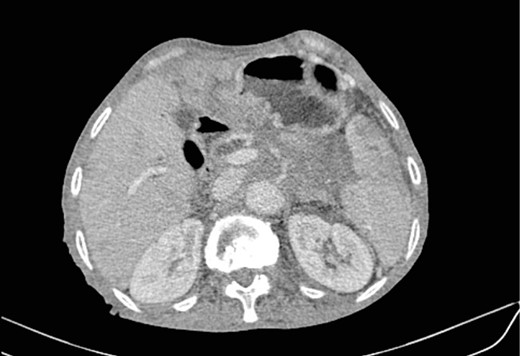

Mr. B. is a 59-year-old patient with no notable pathological history, presenting with melenas associated with marked weight loss. A fibroscopy revealed a thickened and ulcerated gastric mucosa. Abdominal and pelvic CT scans revealed a tissue process in the body and tail of the pancreas invading the splenic hilum, adjacent vessels ans gastric wall, measuring 11 cm long (Fig. 5). A caudal spleno-pancreatectomy enlarged to the colon, omentum and stomach was performed. Macroscopically, the tumor had a grayish–white appearance, poorly limited and indurated on palpation. Histologically, it was a well-differentiated, keratinizing squamous cell carcinoma of the tail of the pancreas (Figs 6 and 7), infiltrating the splenic hilum, gastric wall and colon.

Low enhancing mass at pancreatic body and tail with internal necrotic changes. The mass encases the AMS and its branches and encases splenic vessels. Loss of the fat plane between the mass and adjacent spleen.